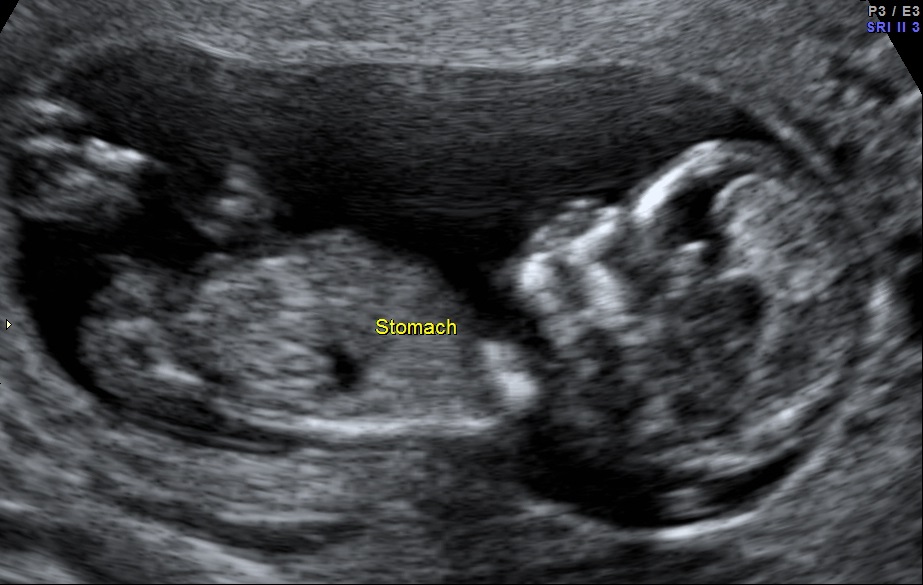

Any gender indicators?

Thread: 12 Weeks, 2 Days

12 Weeks, 2 Days

Boyyy

Boy

Boy!

GUessing blue too but still early